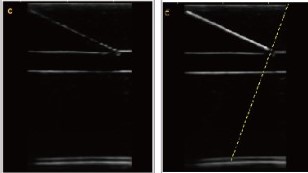

Примеры изображений:

Технология “супер-игла” облегчает проведение биопсии тканей, позволяет четко видеть иглу, что повышает точность и безопасность исследования.